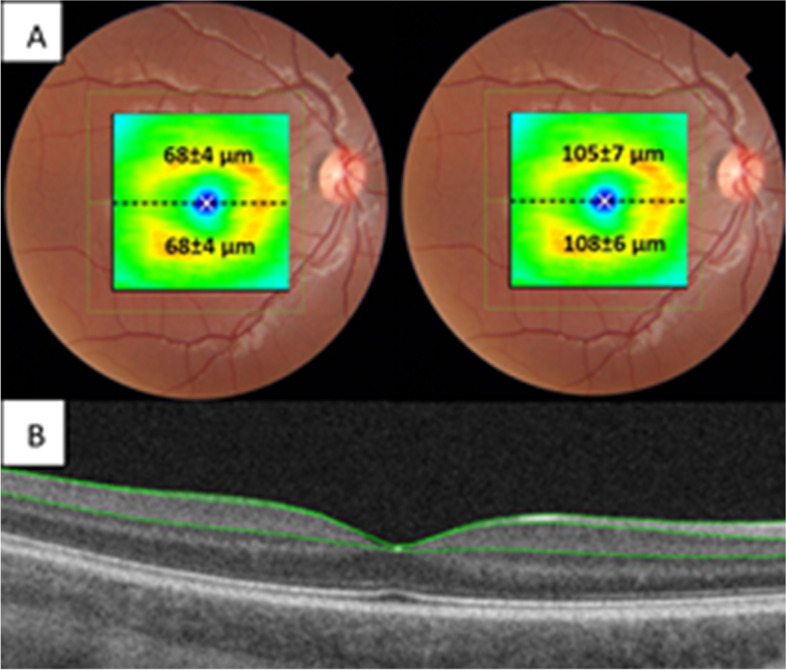

Total mean average for GCIPL was 68.0 μm (sd:4.0, range:58-77) and for GCC was 107.1 μm (sd:6.5, range:92-120). Values for superior and inferior GCL thickness, GCIPL, GCC and segmentation lines are presented in Fig. 1.

Fig. 1.

A. Macular ganglion cell layer (GCL). Average values of superior/inferior GCL-IPL (top left) and GCC (top right) thickness, 7x7mm square measurement shown in figures B. Bottom figure shows segmentation boundaries, ILM (internal limiting membrane) top green line, RNFL/GCL (retinal nerve fibre layer/ganglion cell layer) middle green line, IPL/INL (inner plexiform layer/inner nuclear layer) bottom green line. GCIPL: RNFL/GCL to IPL/INL. GCC: ILM to IPL/INL